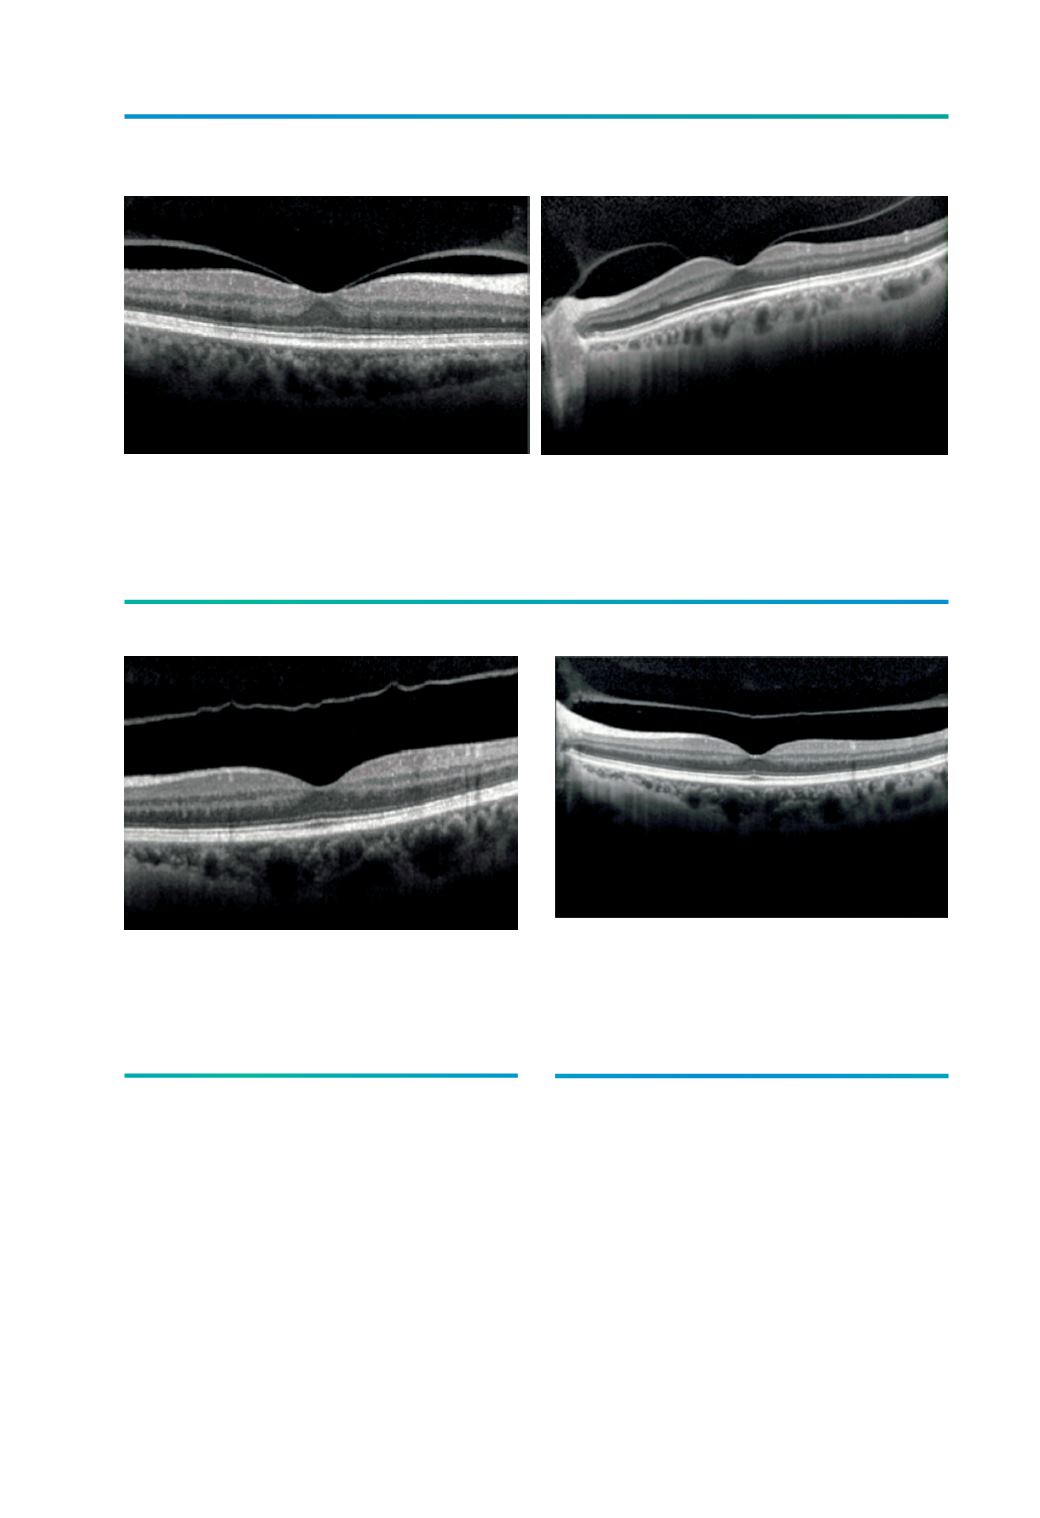

Figura 3.

A) Imagem de tomografia de coerência óptica de doente do sexo feminino de 75 anos mostrando a

separação do vítreo-perifoveal com adesão vítreo-foveolar residual (Estadio 1); B) Imagem de tomografia de

coerência óptica de doente do sexo feminino de 72 anos mostrando a separação do vítreo-perifoveal com

adesão vítreo-foveolar e ao nervo óptico (Estadio 1).

A

B